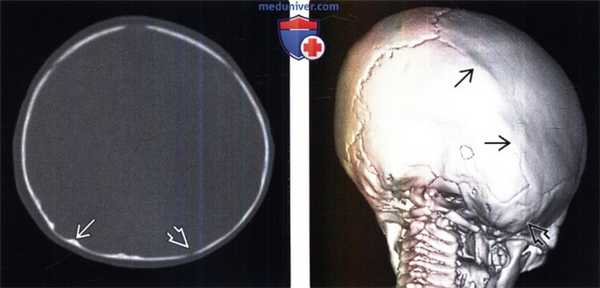

(Слева) КТ головы, костное окно, аксиальный срез: у пациента с односторонним лямбовидным синостозом определяется сращение правого лямбдовидного шва, что вызывает асимметричное уплощение затылочной кости. Левый лямбдовидный шов в норме.

(Справа) КТ, костный режим, косая корональная 3D-pe-конструкция оттененных поверхностей: у этого же пациента подтверждается облитерация лямбдовидного шва справа, что вызывает уплощение затылочной кости и протрузию сосцевидного отростка правой височной кости («сосцевидная шишка»). Лямбдовидный и сагиттальный швы слева открыты.